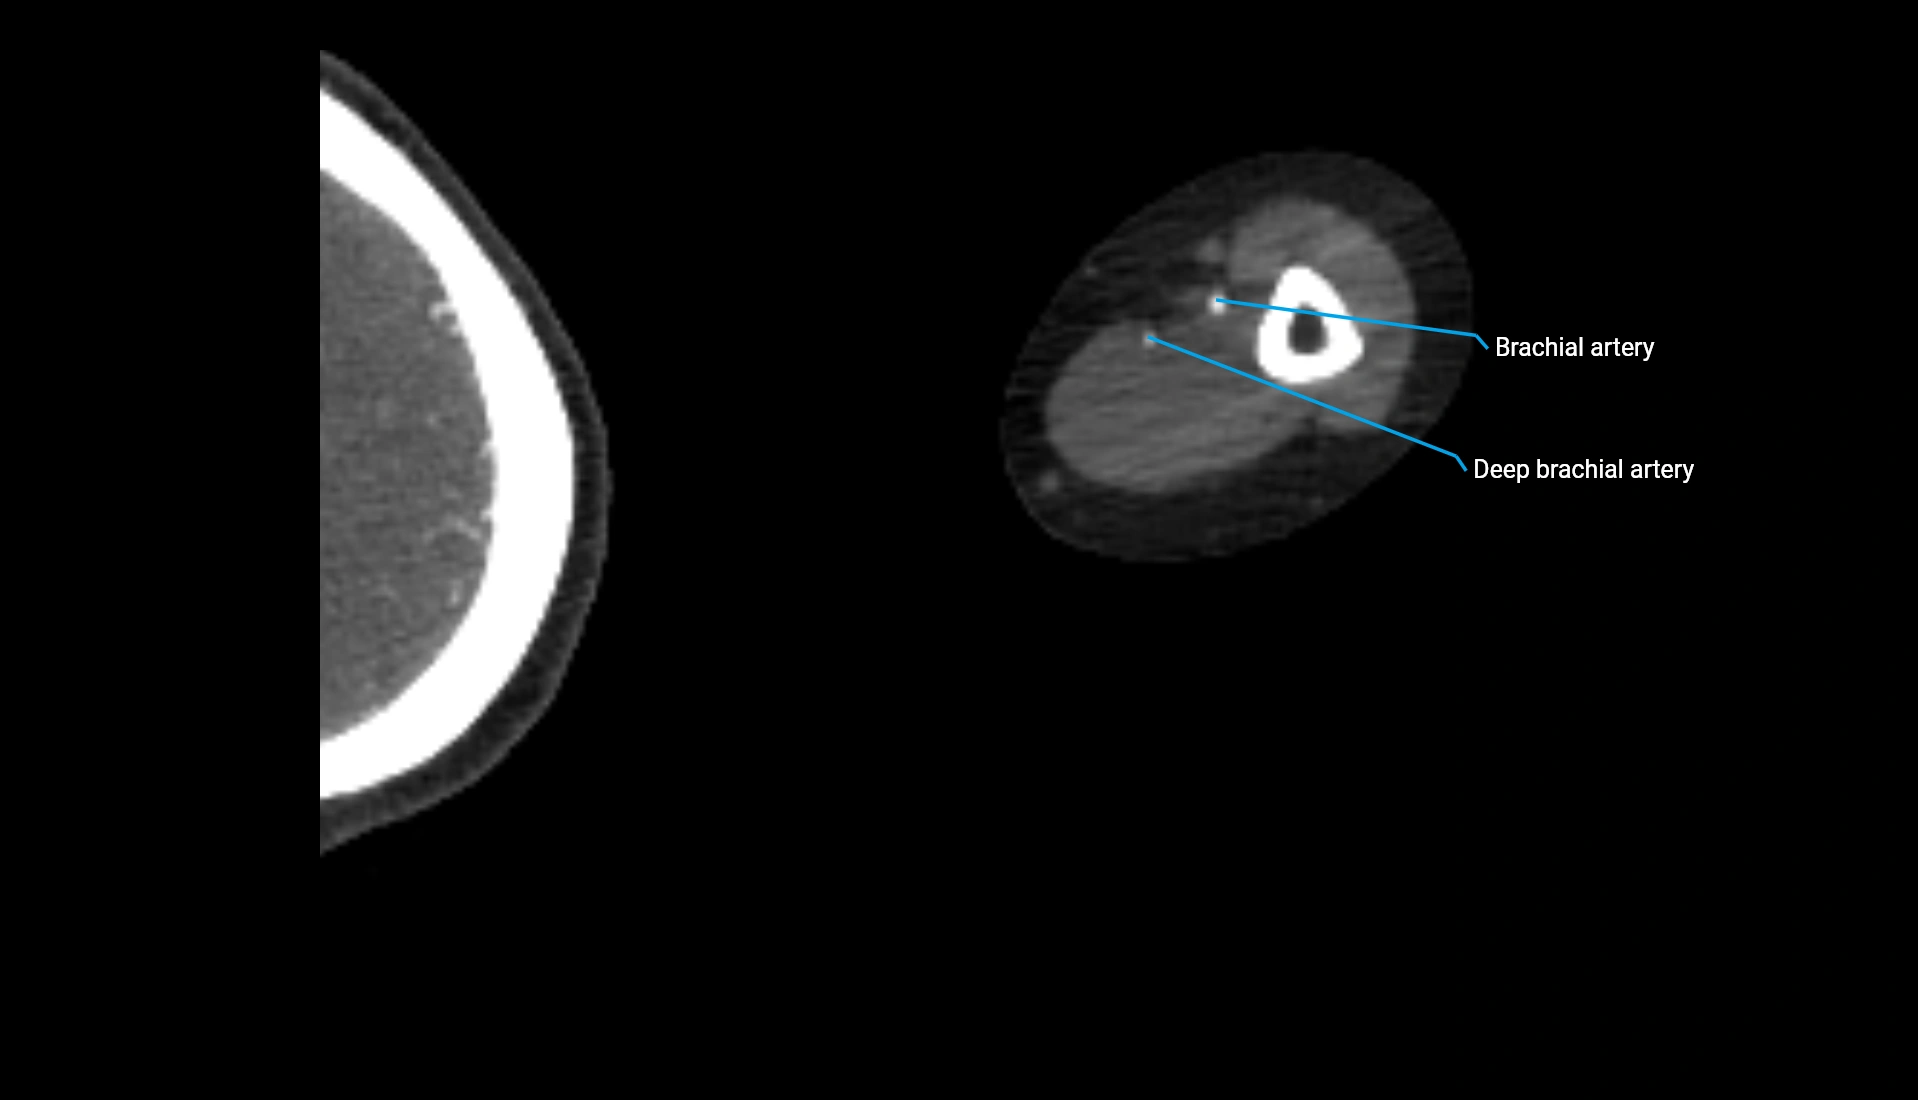

CT Appearance

Non-Contrast CT:

• Cortex: High-density, sharply defined

• Subchondral bone: Dense cancellous matrix

• Articular surface: Smooth concave contour articulating with the capitellum

• Excellent for evaluating bone integrity, alignment, and subtle fractures

Post-Contrast CT:

• Bone: No enhancement

• Joint capsule and synovium: Mild enhancement outlining the joint

• Improves contrast between soft tissues and bony margins

• Useful in detecting subtle joint abnormalities or postoperative changes